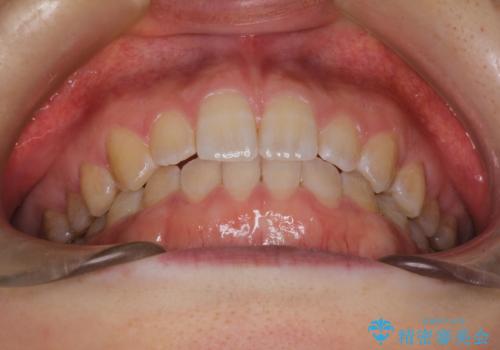

前歯の隙間を閉じたい インビザラインによる矯正

インビザラインにて隙間を閉じる矯正を行いました。

使用時間を守っていただけたので、比較的スムーズに矯正を終了することができました。